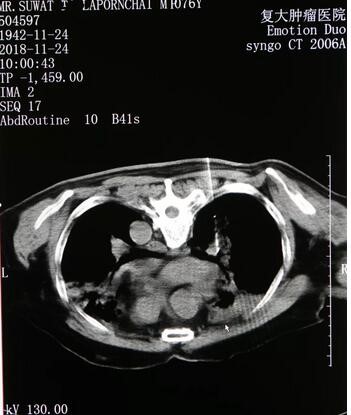

В октябре 2018 года г-н Линь проверил КТ грудной клетки в местной больнице в Таиланде, вызвав «новые метастазы в лимфатические узлы в правом вороте, видя маленькие узелки в правом нижнем легком, учитывая метастазирование», поэтому г-н Линь и его дочь снова приехали в Онкологический госпиталь Фуда. Медициеские эксперты во главе с профессором Ню Личжи обсуждили, и наконец решили делать г-ну Линь биопсию правой челюстной опухоли и криохирургическую абляцию. Операция была очень хорошей: после тестирования размер правого легкого г-на Линь был уменьшен, а после лечения правого легкого воспалительная экссудация в основном абсорбируется. В то же время врач добавил имплантацию новых частиц йода для г-на Линь, и область поражения была меньше, чем раньше.